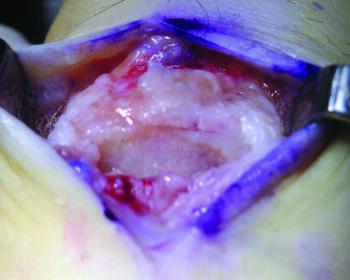

Preoperative radiographs will not always accurately indicate the amount of articular destruction, therefore it is imperative at the time of surgery to visually inspect the articular surface of the first metatarsal head. There may be more or less articular loss than expected by the level of narrowing of the joint space. Often I find the sesamoid apparatus will be “frozen” to the plantar surface of the first metatarsal due to previous injury or fibrosis. After resection of dorsal osteophytes, debridement of chronic synovitis and careful freeing of the sesamoids, the surgeon can re-evaluate the amount of dorsiflexion of the first MPJ. Subchondral drilling may assist where “denuded” cartilage of the metatarsal head is evident.22 Restoration of the articular surface may take place via transplant autograft tissue.23,24 However, there are no reported studies of this advanced procedure in the runner population.

Cheilectomy involves resection of the dorsal exostosis along approximately 1/4 to 1/3 of the dorsal articular surface of the first metatarsal head. Arthroplasty with soft tissue interposition utilizing an acellular dermal matrix is another alternative. Suture can attach the skin substitute to the metatarsal head or positioned within the joint. The matrix will adhere to the metatarsal head and assist with regeneration due to its growth factors, acting as a spacer to prevent recurrent jamming of the joint. In my experience, this procedure reduces the chances for postoperative complications and provides for earlier recovery and rehabilitation of the runner athlete, including less recurrent jamming and earlier, better range of motion of the first MPJ.